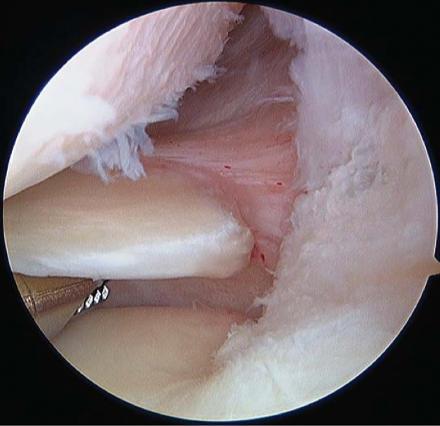

Meniscal root injuries also play a role in the rotational instability of the knee, in particular external meniscal root injuries (35,36). The prevalence of external meniscus root injuries ranges from 6.6%– 13.5% (30,37). These injuries should be diagnosed and treated simultaneously (Figure 8).

In this rotatory instability, there are varying extra-articular lesions of the anterolateral structures and posteromedial capsular plane. Lesion assessment of the medial plane must include both the meniscotendinous complex of the semimembranosus and the medial meniscotibial ramp. The semimembranosus is likely to be involved in the physio-pathogenesis of a medial meniscal ramp injury because of its anatomical relationship with the posterior segment of the medial meniscus and the meniscotibial ligament (33). Thus, according to Hughston, the reflex contraction of the semimembranosus during trauma from excessive anterior tibial subluxation secondary to ACL rupture stresses the posteromedial capsule while the meniscus is trapped between the femur and tibia, leading to tears in the meniscocapsular and/or meniscotibial ligaments (34). These lesions correlate with a high-grade pivot shift so it is important to look for and include them in surgical planning to restore the rotational kinematics of the knee (32).